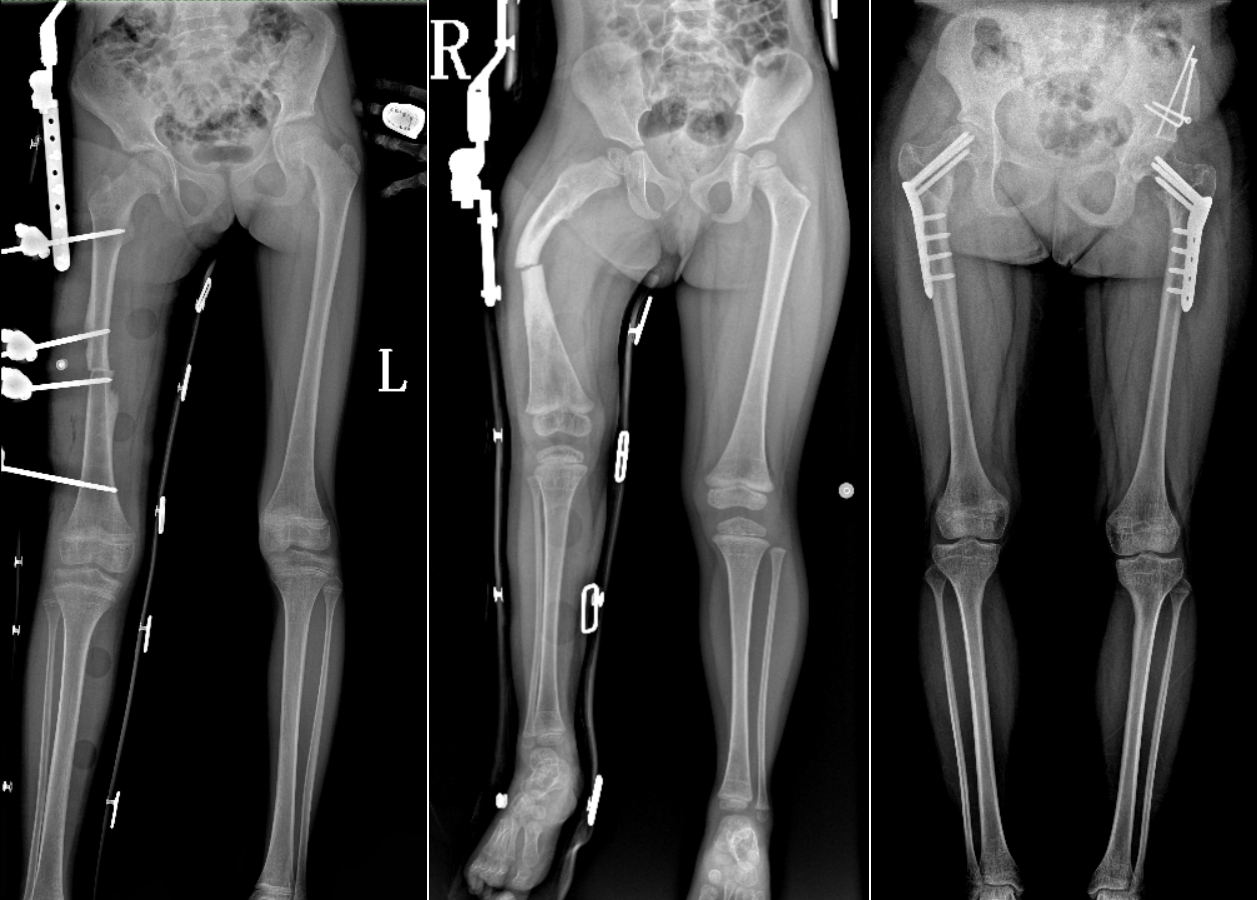

DR是临床骨科的重要检查手段之一。在骨科检查中,脊柱矫形、长骨骨折、腰椎退行性病变等,需要采集脊柱、下肢全景图像,辅助医生临床诊断,从而制定科学的治疗方案,糖心vlog 的大视野平板动态DR就像是一座桥梁,连接起现代医疗技术与当地人民的医疗需求。

糖心vlog 自主研发的大视野平板动态,采用17"*34"的有效视野,一次曝光即可得到全脊柱或全下肢影像。相较于多张摄影再软件拼接的DR设备,PLX8600解决了拼接图像存在密度不均匀,拼接处图像配准和放大效应等问题,给临床带来了真正的大视野影像解决方案。

除了常规静态摄影外,PLX8600的大平板具备动态透视和点片功能,能够很好地观察复杂部位病灶,有效地抓取关键帧,降低患者多次摄片的概率。如:全脊柱状态评估、长骨关节活动度、下肢静脉造影瓣膜功能评估、消化道功能评估、脊髓造影等更多大视野临床应用,“多面手”都能轻松应对。